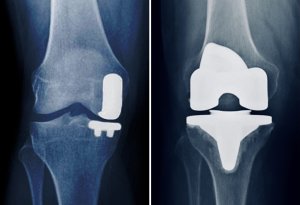

Tipologie di protesi al ginocchio

Esistono diversi tipi di protesi, a seconda della gravità del danno articolare e delle condizioni del paziente:

1. Protesi Totale

• Sostituisce l’intera articolazione del ginocchio.

• Indicata per pazienti con artrosi avanzata o danni diffusi.

2. Protesi Monocompartimentale

• Sostituisce solo una parte del ginocchio (mediale o laterale).

• Richiede una cartilagine ancora in buono stato nelle altre zone.

3. Protesi di Revisione

• Indicata nei casi in cui una protesi precedente abbia fallito o si sia deteriorata.

Il chirurgo ortopedico valuterà la soluzione migliore in base al quadro clinico del paziente.

L’intervento di protesi totale al ginocchio

L’intervento si svolge sotto anestesia spinale o generale e dura circa 60-90 minuti. Le fasi principali sono:

1. Incisione dell’articolazione: il chirurgo accede al ginocchio rimuovendo le parti danneggiate dell’osso e della cartilagine.

2. Impianto della protesi: vengono posizionati componenti metallici e in polietilene biocompatibili.

3. Stabilizzazione dell’articolazione: la protesi viene fissata con cemento osseo o metodologie senza cemento.

4. Chiusura dell’incisione e bendaggio dell’area trattata.